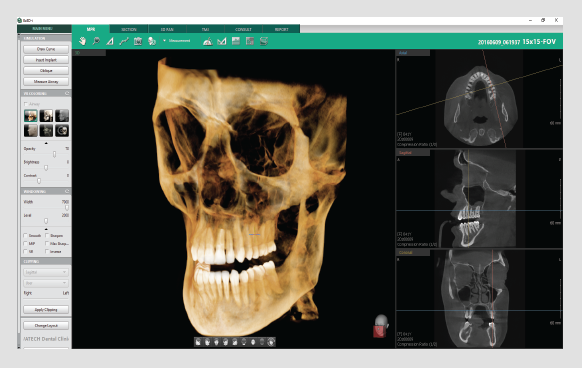

Powered by a new 3D VR graphics engine, the Ez3D-i is the ideal tool to effortlessly obtain the correct perspectives needed for accurate and true-to-measurement diagnosis.

• Various VR coloring modes and 2D filters

• Intuitive implant simulation tools for collision detection (implant/canal), bone density verification, and oblique viewing tools

• 3D panoramic navigation

Quickly and easily switch between multiple VR views